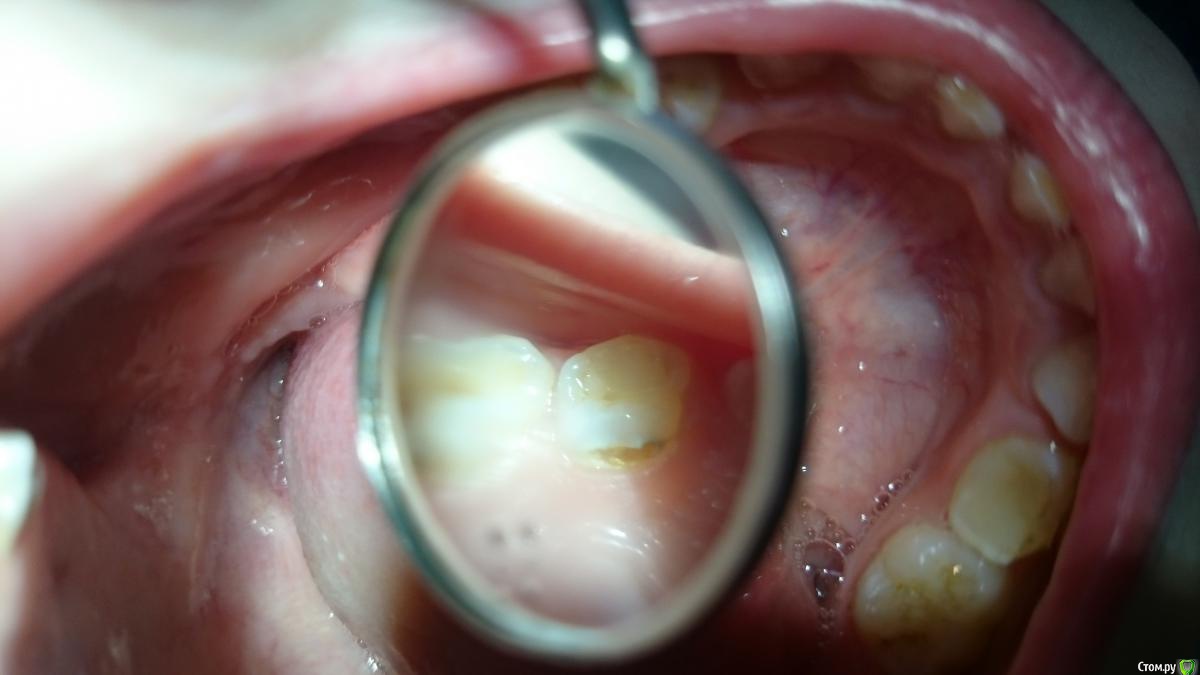

crown Опубликовано 11 октября, 2016 Поделиться Опубликовано 11 октября, 2016 4,5 года, зуб 6.4 полость на небной поверхности в пришеечной области, аналогично поражены все моляры верхней челюсти. Из анамнеза: мама рожала под общим обезболиванием. Кариес? Но откуда он там взялся? Гипоплазия? Да и главный вопрос, возможно ли ограничиться реставрацией? Ссылка на комментарий

Kota Опубликовано 12 октября, 2016 Поделиться Опубликовано 12 октября, 2016 это кариес. причина скорее всего долгая бутылочка ночью. лечить однозначно. выбор материала зависит от поведения. если удастся сделать ретракцию ниткой, то фото. если нет, то витремер будет стоять. Ссылка на комментарий

krokomot Опубликовано 12 октября, 2016 Поделиться Опубликовано 12 октября, 2016 Kota Я думал бутылочка только фронт сноситСладкое питье сносит всю пришейку верхних, у меня был такой любитель персикового сока все пришейки верхних зубов НЕБНО! были в кариесе Ссылка на комментарий

Kota Опубликовано 12 октября, 2016 Поделиться Опубликовано 12 октября, 2016 Kota Я думал бутылочка только фронт сносит[/quoteКак раз небные поверхности всех зубов и вестибулярные резцов. Ссылка на комментарий

Kota Опубликовано 12 октября, 2016 Поделиться Опубликовано 12 октября, 2016 Kota Я думал бутылочка только фронт сноситС соской контактирует как раз небная поверхность. Вестибулярка повреждается за счет уздечки и особенности предверия в той области. Ссылка на комментарий